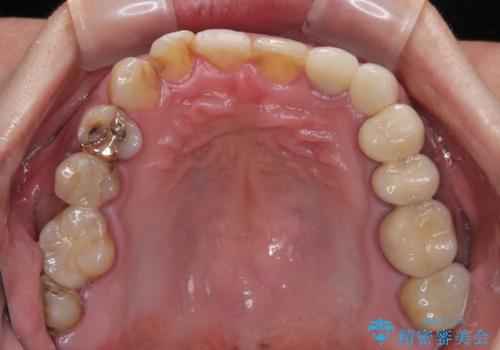

- すぐに欠けてしまう前歯や、むし歯で全顎的に処置された歯を気にして来院された患者様です。

元来むし歯が多く、さらに受け口傾向の咬み合わせを気にしていらっしゃいました。

当初はむし歯処置が必要な歯のみの治療予定でしたが、捻転や咬み合わせを可及的に改善したいとのことで、全顎的にオールセラミッククラウンにて補綴治療を行うこととしました。